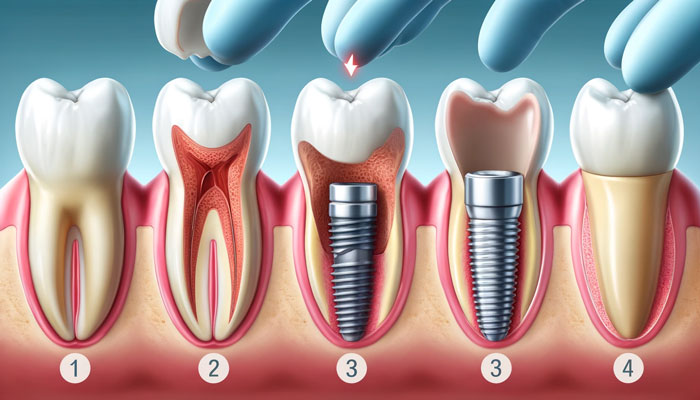

ایمپلنت دندان به یک پایه تیتانیومی یا زیرکونیایی گفته میشود که در استخوان فک قرار میگیرد و به عنوان ریشه دندان مصنوعی عمل میکند. این پایه با گذشت زمان به استخوان فک جوش میخورد و پایداری لازم را برای نگهداری تاج دندان مصنوعی فراهم میکند. ایمپلنتها در انواع مختلفی از جمله تک، چندگانه و کامل موجود هستند که بسته به نیاز بیمار انتخاب میشوند.

ایمپلنت فوری، روشی است که در آن پایه ایمپلنت بلافاصله پس از کشیدن دندان آسیبدیده یا از دست رفته، در استخوان فک قرار میگیرد. این روش به بیمار این امکان را میدهد که در یک جلسه دندان جدید خود را دریافت کند. ایمپلنت فوری به دلیل کاهش زمان درمان و جلوگیری از تحلیل استخوان، گزینهای جذاب برای بسیاری از بیماران است.